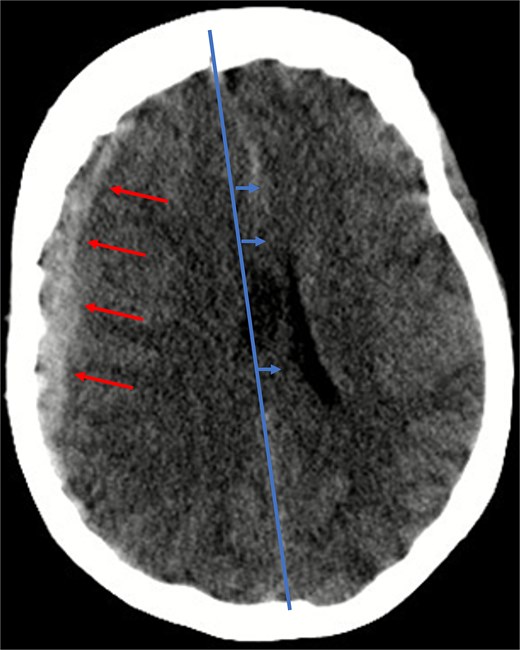

Given her anticoagulated state, a cranial computed tomography (CT) scan was performed, in line with departmental protocols for patients with head trauma on anticoagulation. The scan revealed a 13 mm-wide subdural hematoma spanning the entire right hemisphere, accompanied by an 8 mm midline shift, and near-complete collapse of the right lateral ventricle (Fig. 1). Additionally, diffuse cerebral swelling was also present. There were no signs of skull fractures or ischemia.

Illustration of a hyperdense, concave 13 mm wide mass as an expression of a subdural hematoma in the right hemispheric region (red arrows) and a consecutive midline shift of 8 mm due to edema (blue arrows).